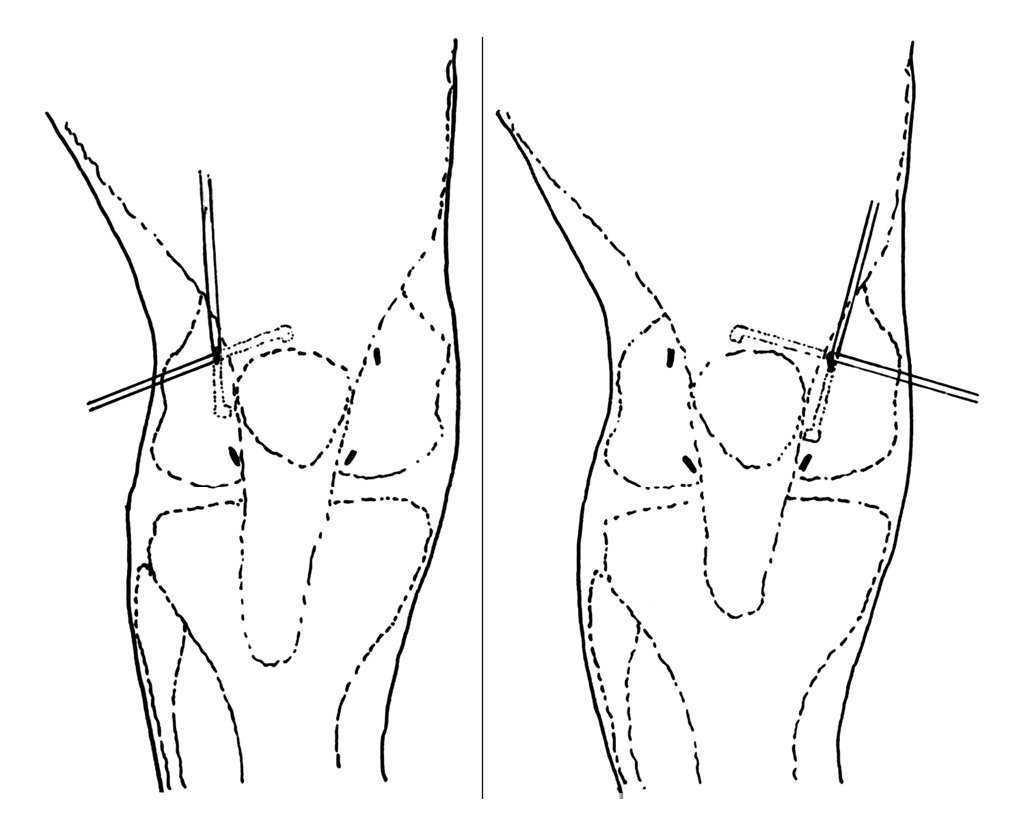

En todos los pacientes se practicó una artroscopia diagnóstica en el transcurso de la cual se realizó una denervación rotuliana artroscópica10. Los portales utilizados han sido los habituales (anteroexterno y anteromedial): a través de la vía anteroexterna es posible visualizar la práctica totalidad de las carillas articulares de la rótula. Estos portales se pueden suplementar con otros suprarrotulianos (externo e interno). El instrumental es introducido a través de las vías anterointerna o suprarrotulianas. Gracias a la combinación de los abordajes artroscópicos descritos se puede acceder a la totalidad del perímetro rotuliano para realizar una lesión térmica, con un electrocoagulador artroscópico, en el tejido blando perirrotuliano más próximo a la rótula (fig. 1). En todos los casos se ha dejado intacta (sin lesión térmica) la región que corresponde al tendón rotuliano, ya que por una parte es más difícil su visualización artroscópica por la presencia de la grasa de Hoffa, en ocasiones hipertrofiada, y por otra se ha considerado que puede comportar un alto riesgo de lesión del tendón rotuliano y de los vasos que nutren la rótula a través de él.

Figura 1.Combinando los diferentes portales suprarrotulianos y anteriores, el electrocoagulador puede acceder fácilmente al tejido blando perirrotuliano.